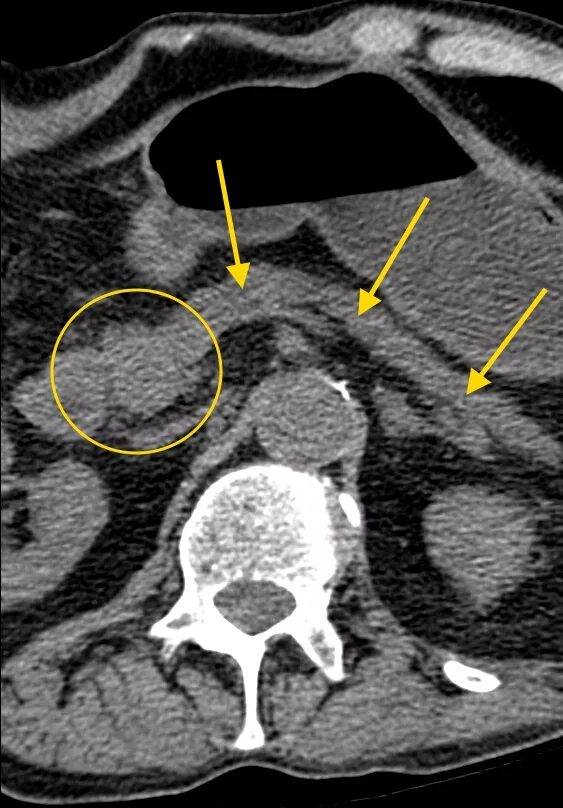

Расширен проток